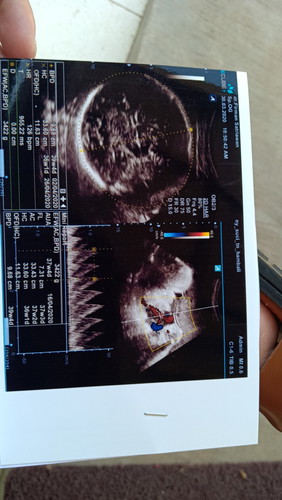

bayi terlilit talipusar 2x

Bismillah. MasyaAllah tabarakallah. Usia kehamilan saat ini 37week. Pengen banget lahiran normal, tapi dokter menyarankan sc karena bayi terlilit tali pusat 2x di leher. Pas denger dokter bilang gitu sedih rasanya :( Bagaimana dengan ibu2? Ada yg tau ga caranya lepasin lilitan tali pusar supaya bisa lahiran normal dan bayi keluar dengan sehat selamat.